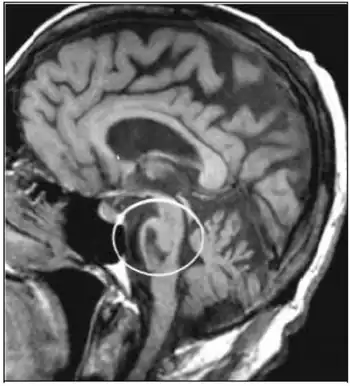

Locked-in syndrome can be caused by a stroke at the level of the basilar artery denying blood to the pons, among other causes. | |

Unlike persistent vegetative state, in which the upper portions of the brain are damaged and the lower portions are spared, locked-in syndrome is essentially the opposite, caused by damage to specific portions of the lower brain and brainstem, with no damage to the upper brain. Injuries to the pons are the most common cause of locked-in syndrome.

- A stroke or brain hemorrhage, usually of the basilar artery